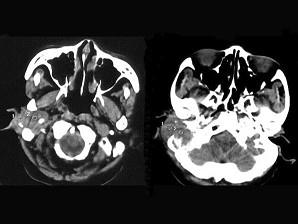

女,56岁,右侧中耳术后发现右外耳道新生物一年,PE:右外耳道内段被新生物充满,CT如图所示,应诊断为 ( )